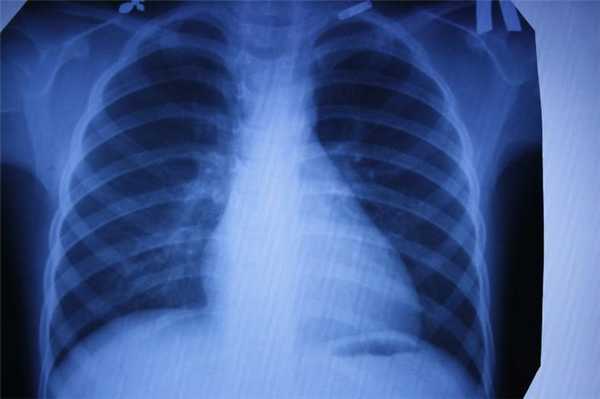

Что покажет рентген

Рентген - это самый широко доступный тип обследования. В Санкт-Петербурге его можно сделать быстро на платной или бесплатной основе как в частных, так и в государственных клиниках и больницах. Основная задача рентгенографии - дать общее представление об изменении структуры органов и костной ткани. С помощью рентген-аппарата врач может хорошо визуализировать:

- инородные тела;

- переломы;

- воспаление легких;

- рак молочной железы;

- туберкулез.

Основное преимущество рентгенографии заключается в том, что это быстрый и дешевый метод сканирования. Однако по точности и диагностической ценности он безусловно уступает как УЗИ, так и таким высокотехнологичным методам исследования, как МРТ и КТ.

В основе физики работы рентген-аппарата лежат просвечивающие способности рентгеновских лучей. Получение плоского двухмерного изображения основано на ослаблении рентгеновского излучения при его прохождении через различные ткани. При рентген-сканировании пучок излучения, проходя через ткани организма, которые обладают различной плотностью, рассеивается и тормозится. Таким образом, на пленке возникают изображения разной степени интенсивности. Лучевая нагрузка при рентгенографии небольшая, но она всегда есть и может составлять от 0,1 до 1 мЗв. Поэтому рентгенография запрещена для беременных женщин, а здоровому человеку рентген можно делать 1- 2 раза в год.

Кроме дозы облучения у рентгеновского сканирования есть один существенный диагностический недостаток - плоская картинка. Поскольку рентген изображения - это тень ткани на пленке, объемно оценить органы и структуры человеческого тела с помощью рентгена не получается.